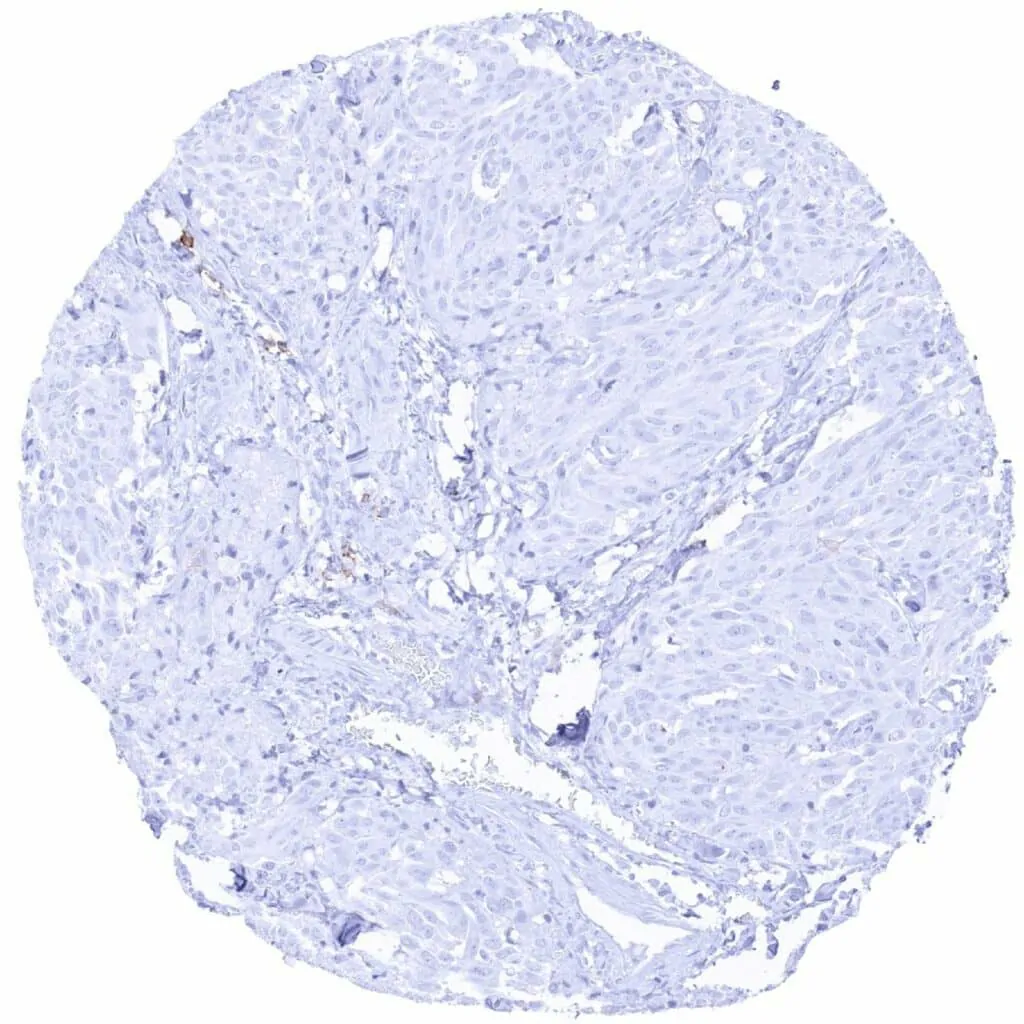

Soft tissue – CD38 negative leiomyosarcoma